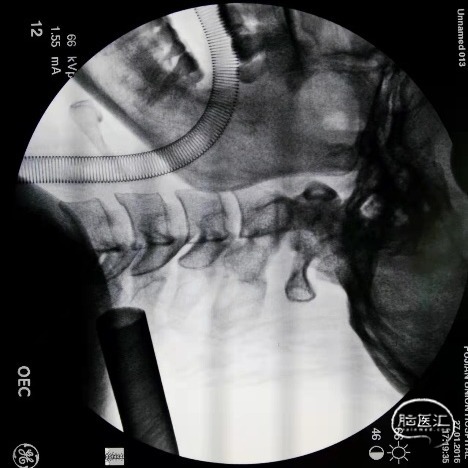

图4术中透视定位建立微通道,通过调整微通道角度,行椎板开窗切除黄韧带。